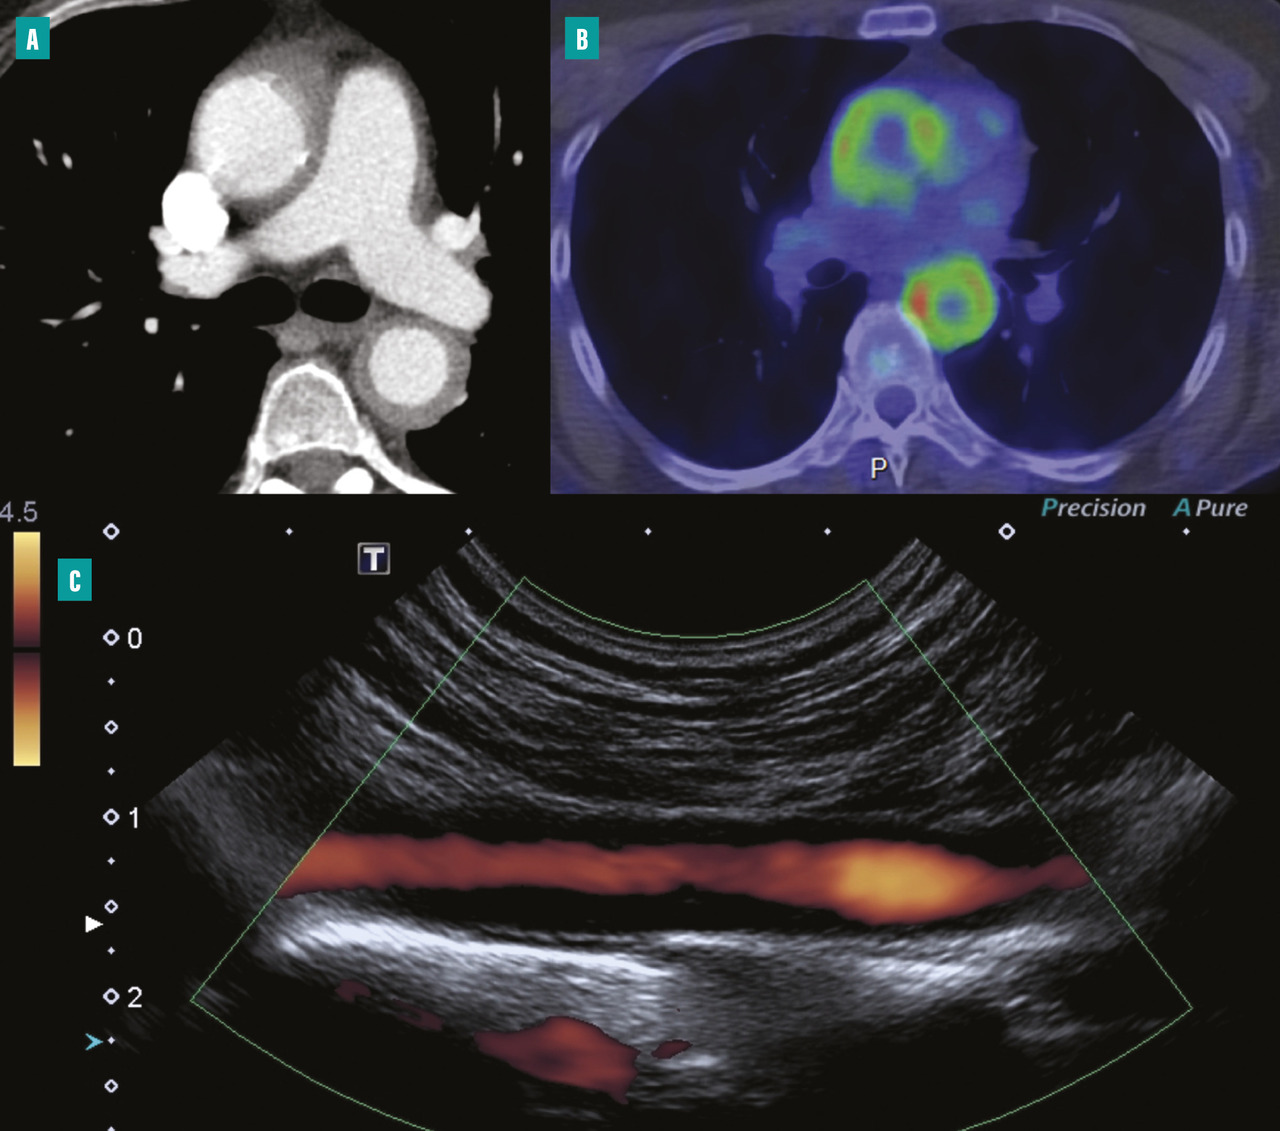

Échographie Doppler pour les artères des membres et les troncs supra-aortiques

L’échographie-Doppler artérielle est un examen non invasif de première intention permettant d’explorer les artères des membres et les troncs supra-aortiques.15 Elle peut mettre en évidence un épaississement circonférentiel et homogène de la paroi artérielle, une sténose artérielle et son éventuel retentissement hémodynamique d’aval, une occlusion artérielle ou un anévrisme (fig. 2 ).

Angioscanner pour l’aorte et ses branches

Par rapport à l’échographie-Doppler artérielle, l’angioscanner artériel a l’avantage de pouvoir explorer la portion thoracique de l’aorte. À la phase aiguë inflammatoire, on peut observer un épaississement pariétal supérieur à 3 mm, parfois une prise de contraste pariétale qui correspond à un rehaussement homogène au temps tardif de l’injection.16

Tomographie par émission de positons au 18F-FDG

La tomographie par émission de positons au 18-flurodésoxyglucose (TEP 18F-FDG) a un intérêt dans le diagnostic de la maladie, notamment dans la phase active, afin d’affirmer le caractère inflammatoire d’une aortite et la localisation précise des segments atteints, notamment chez des patients porteurs d’une forme clinique fruste. La fréquence de l’atteinte artérielle en TEP oscille entre 35 et 60 % des patients selon les études.16

Dans le suivi, elle constitue également un argument supplémentaire à l’évaluation de l’activité de la maladie en cas de positivité, toujours à confronter à l’évaluation clinique et biologique du patient.